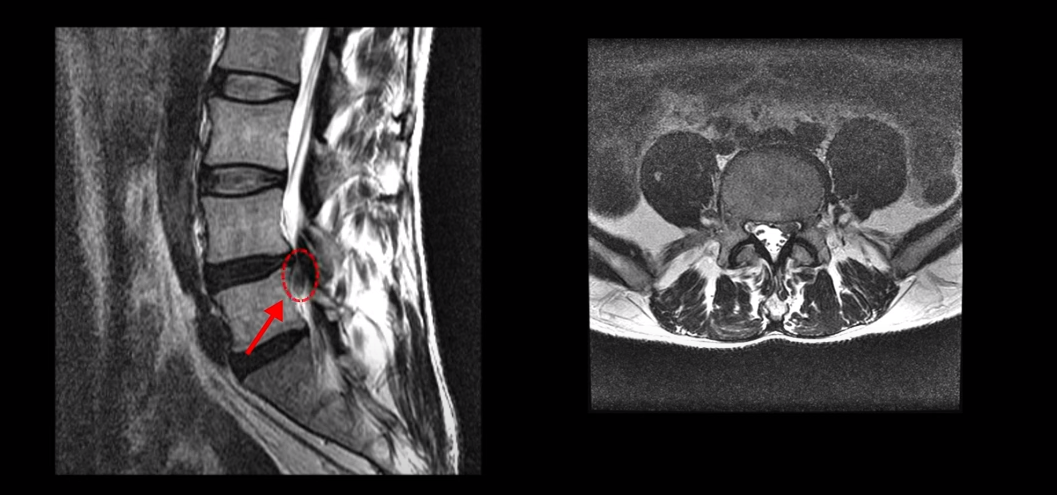

이 환자분에 대해 더 자세히 설명 드리겠습니다. 이분은 약 40일 전 농장에서 풀 뽑기를 한 후 허리디스크가 심하게 파열되어 극심한 방사통과 감각 마비가 생깁니다. 이분 MRI를 보면 4번 5번 마디가 심하게 파열되어 수핵이 아래로 많이 흘러내려 있습니다.

수핵이 왼쪽으로 밀려나와 있어서 극심한 왼쪽 다리 방사통과 감각 마비가 있습니다.